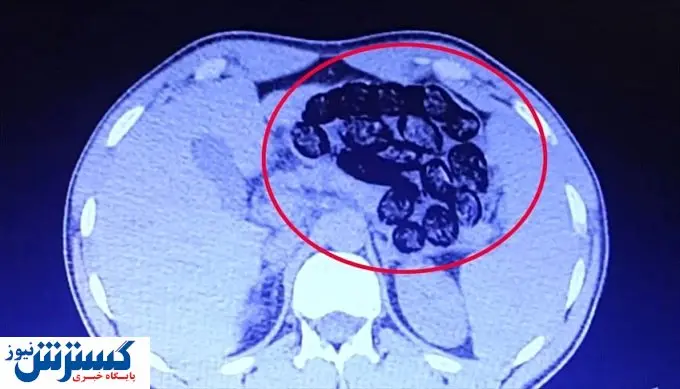

پلیس ترکیه دو شهروند ایرانی که ۹۲۰ گرم مواد مخدر را در قالب ۱۰۳ بسته در معده خود حمل می‌کردند تا از شهر وان به ازمیر بروند دستگیر کرد.

اداره امنیت استان وان ترکیه با انتشار اطلاعیه‌ای اعلام کرد پلیس این استان دو شهروند ایرانی که ۹۲۰ گرم مواد مخدر را در قالب ۱۰۳ بسته در معده خود حمل می‌کردند، دستگیر کرده است.

طبق اطلاعیه فوق٬ این شهروندان ایرانی قصد داشتند از فرودگاه فرید ملن شهر وان به ازمیر بروند که از سوی پلیس مبارزه با مواد مخدر شناسایی شده‌اند.

پلیس ترکیه پس از دستگیری این افراد، آنها را به بیمارستان منتقل کرده و ۹۲۰ گرم مواد مخدر موجود در معده آنها خارج شد.